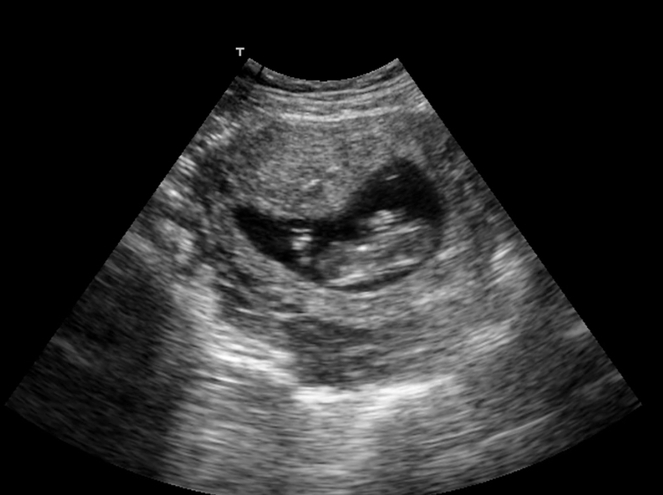

Nun wissen es endlich alle! - Tagebücher aus der Schwangerschaft von Sandra aus Stuttgart